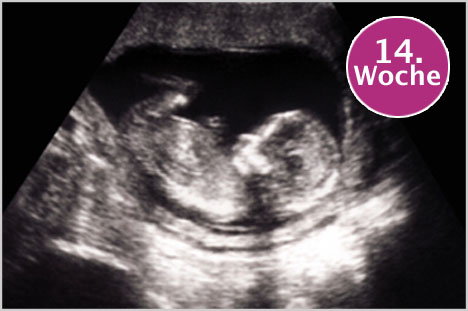

Meleklerim ben yarindan itibaren 14. haftama girecegim icin ve her hafta

ne durumda ve bendeki degisiklikler normalmi diye internetten arastirdigim icin, bundan sonra sizinle paylasmaya karar verdim... Bilmiyorum bebegin anne karnindaki görüntüsü nasildir diye merak ediyorum ve inceliyorum...